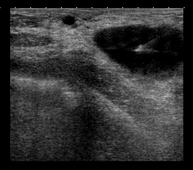

Ultrasound-guided CNB (core-needle biopsy)

A core-needle biopsy or core biopsy involves obtaining a cylinder of tissue for histological study. Under ultrasound guidance and after administering local anaesthesia, the needle is placed in the area to be studied and, using an automatic cutting system, several millimetre-long cylinders of tissue are obtained. It is a relatively short and relatively painless procedure. It allows a significant sample to be obtained for histological study.

Gold seeding for radiotherapy

It consists of marking diagnosed cancer lesions to indicate their exact location in order to apply radiotherapy selectively so that it affects the tumour with minimal impact on neighbouring tissues. This procedure is performed under ultrasound guidance, locating the tumour and inserting the gold seeds (3 to 4 seeds) as markers at four points around its periphery.